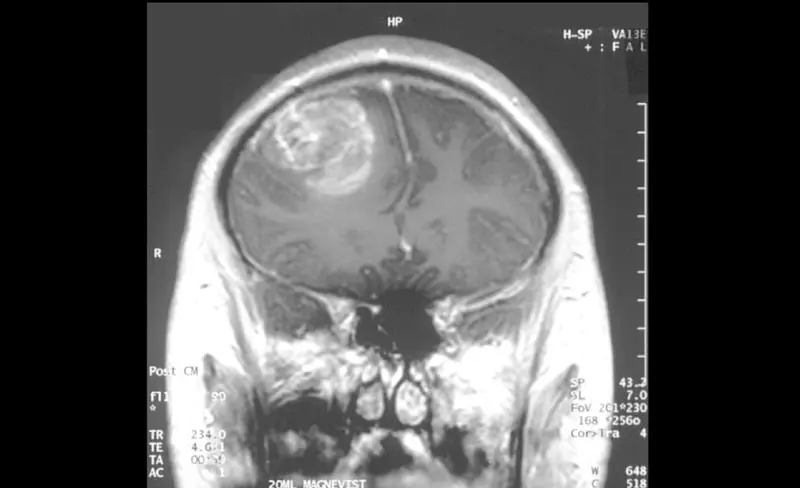

MRI of a glioblastoma – CC 2.5. Christaras A

Mills y su equipo identificaron un talón de Aquiles de los glioblastomas, que no solo podría conducir a mejores tratamientos, sino que también explicaría en parte por qué estos y otros cánceres son tan agresivos.

Se descubrió que la proteína 8 que contiene bromodominio, o BRD8, suprime la actividad de una de las partes más importantes de una célula para prevenir el cáncer, el gen P53. P53 codifica proteínas que impiden que las células se dividan cuando de lo contrario deberían morir, y casi todos los cánceres dependen de interrupciones en la actividad o producción de P53.

En experimentos, los investigadores desactivaron BRD8 utilizando una técnica pionera de edición de genes. Sin BRD8 hiperactivo, las proteínas P53 se codificaron normalmente de nuevo, y los tumores, trasplantados a ratones de pacientes humanos, se detuvieron en seco.

Cuando se desactivó BRD8, se desbloqueó P53: los tumores dejaron de crecer y los roedores vivieron más tiempo.